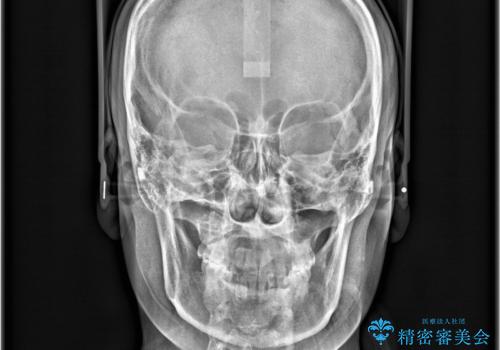

下顎前歯の叢生がとれ右上2の反対咬合も改善し患者様にも満足していただけました。治療期間は1年~1年半を見込んでいましたが、患者様の協力もあり10か月で矯正を終えることが出来ました。

インビザラインはご自身でマウスピースをはめて頂く矯正なので、マウスピースの使用時間をきちんと守れているかどうかがとても大事になります。

インビザラインの性質上、食いしばりや歯ぎしりがある方は咬み合わせが甘くなることがあります。そのような時は保定装置にベックタイプのリテーナーを組み合わせることで改善できます。